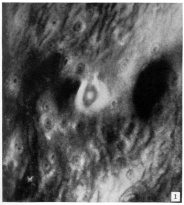

Surface view of implantation site